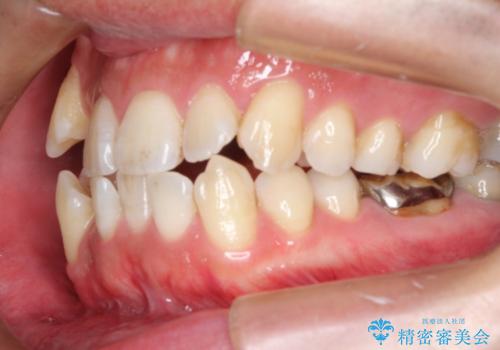

初診時の歯並びの状態としては、右上の犬歯がいわゆる八重歯の状態であり、強いガタガタが上下ともにある状態でした。

若干の口元の突出感もあったため、抜歯によるスペースを利用し、がたつきの改善と前歯の後退をを行いました。

見た目、嚙み合わせ及び、治療期間や施術内容にご満足いただきました。